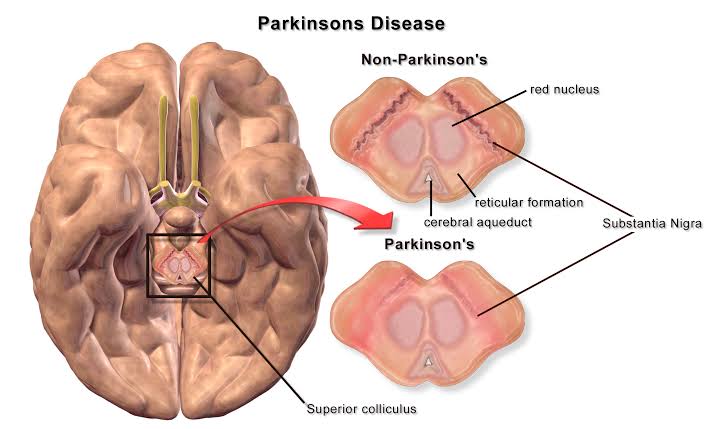

The cause of Alzheimer disease is unknown. Scientists know that in Alzheimer disease there is large build-up of proteins called amyloid within brain cells. These proteins occur normally, but not yet understand why they build up in large amounts. The disease process can go on for many years without symptoms, but as more and more proteins form brain cells,the cells lose their ability to function and eventually die. This causes the affected parts of the brain to shrink.